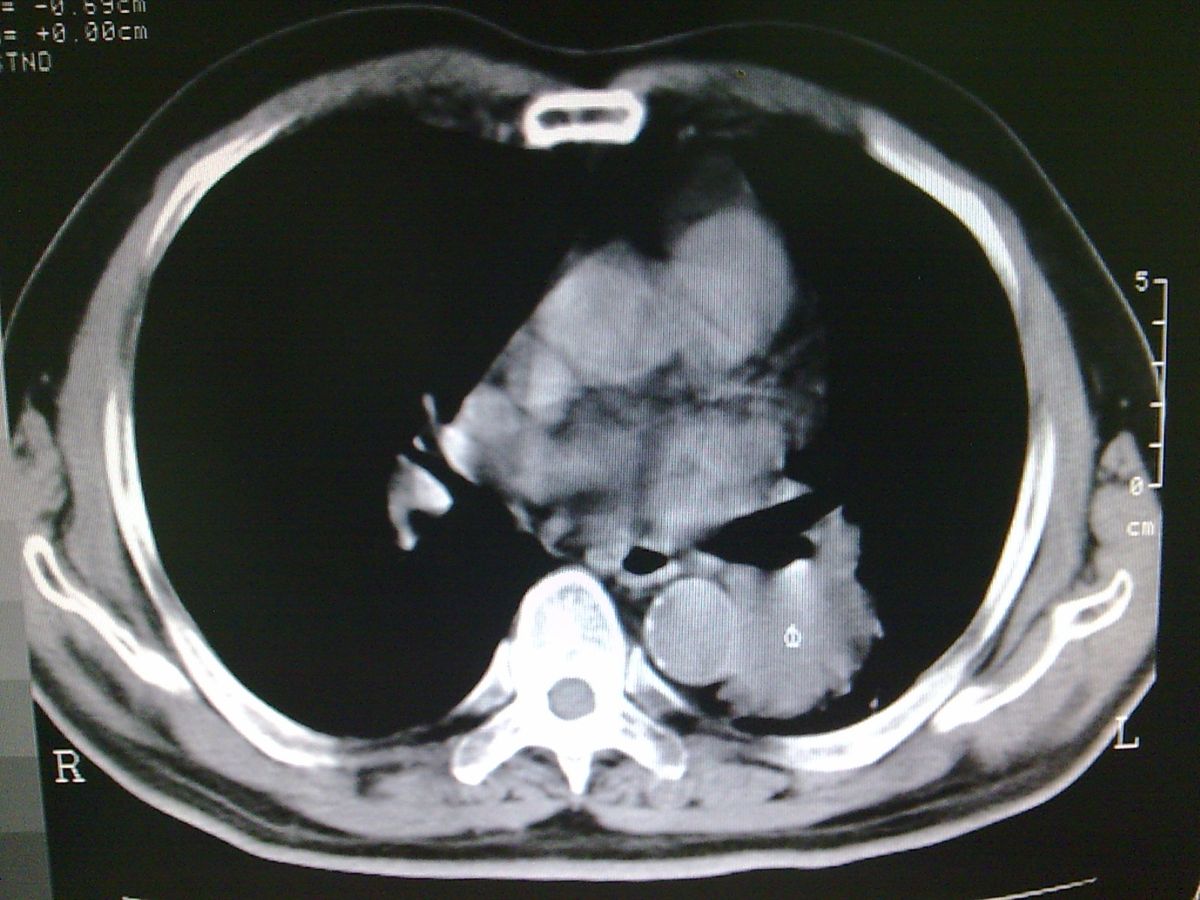

标题: CT19282:男性,70岁,咳血, [打印本页]

标题: CT19282:男性,70岁,咳血,

图片少了些,考虑周围性肺癌

考虑周围性肺癌

周围型肺癌。

考虑周围型肺癌,还是做增强扫描吧。

考虑左下肺周围性肺癌。

隔离症不像吗.周围型肺癌?还是做增强扫描吧。

肺隔离症不除外建议增强扫描

考虑左肺下叶周围型肺癌可能。